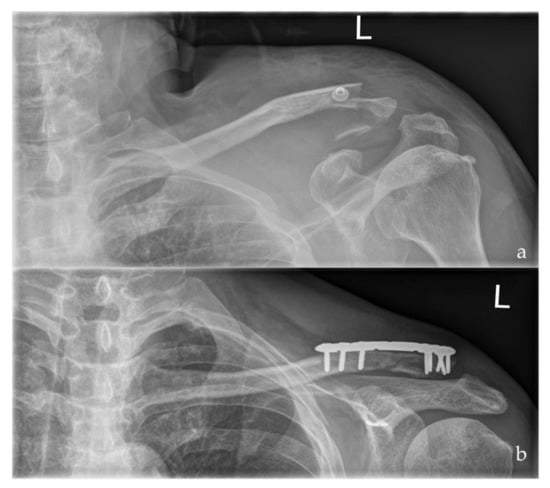

Figure 2. Preoperative (a) and postoperative (b) radiographs of a left sided multi-fragmentary, displaced lateral clavicle fracture (Neer IIb) after arthroscopic assisted ORIF using a LCP and the knotless DogBone Technique (Group II).

The lateral clavicle fractures were addressed using a locking compression plate (Arthrex®, Naples, Florida, USA) and the coracoclavicular ligament injury was taken care of either by a knotted or knotless DogBone ™ (Arthrex, Naples, Florida, USA) Button technique, respectively (Figure 1 and Figure 2). A small longitudinal skin incision was carried out to address the lateral clavicle fracture. The fracture was reduced and stabilized using a locking compression plate. A routine diagnostic arthroscopic procedure followed by preparation of the coracoid base was performed. For preparation of the base of the coracoid process care has to be taken of the subscapularis tendon which lies below and directs medially to the coracoid process. Furthermore, the glenoid labrum should not be damaged during preparation. The musculocutaneous nerve must be taken care of as it lies medial to the coracoid base, why subtle preparation has to be performed in this region. The DogBone™ Button was inserted and either knotted (Group 1) or locked using a knotless (Group 2) technique. These two techniques have been compared to each other with respect to functional outcome and irritation rates.